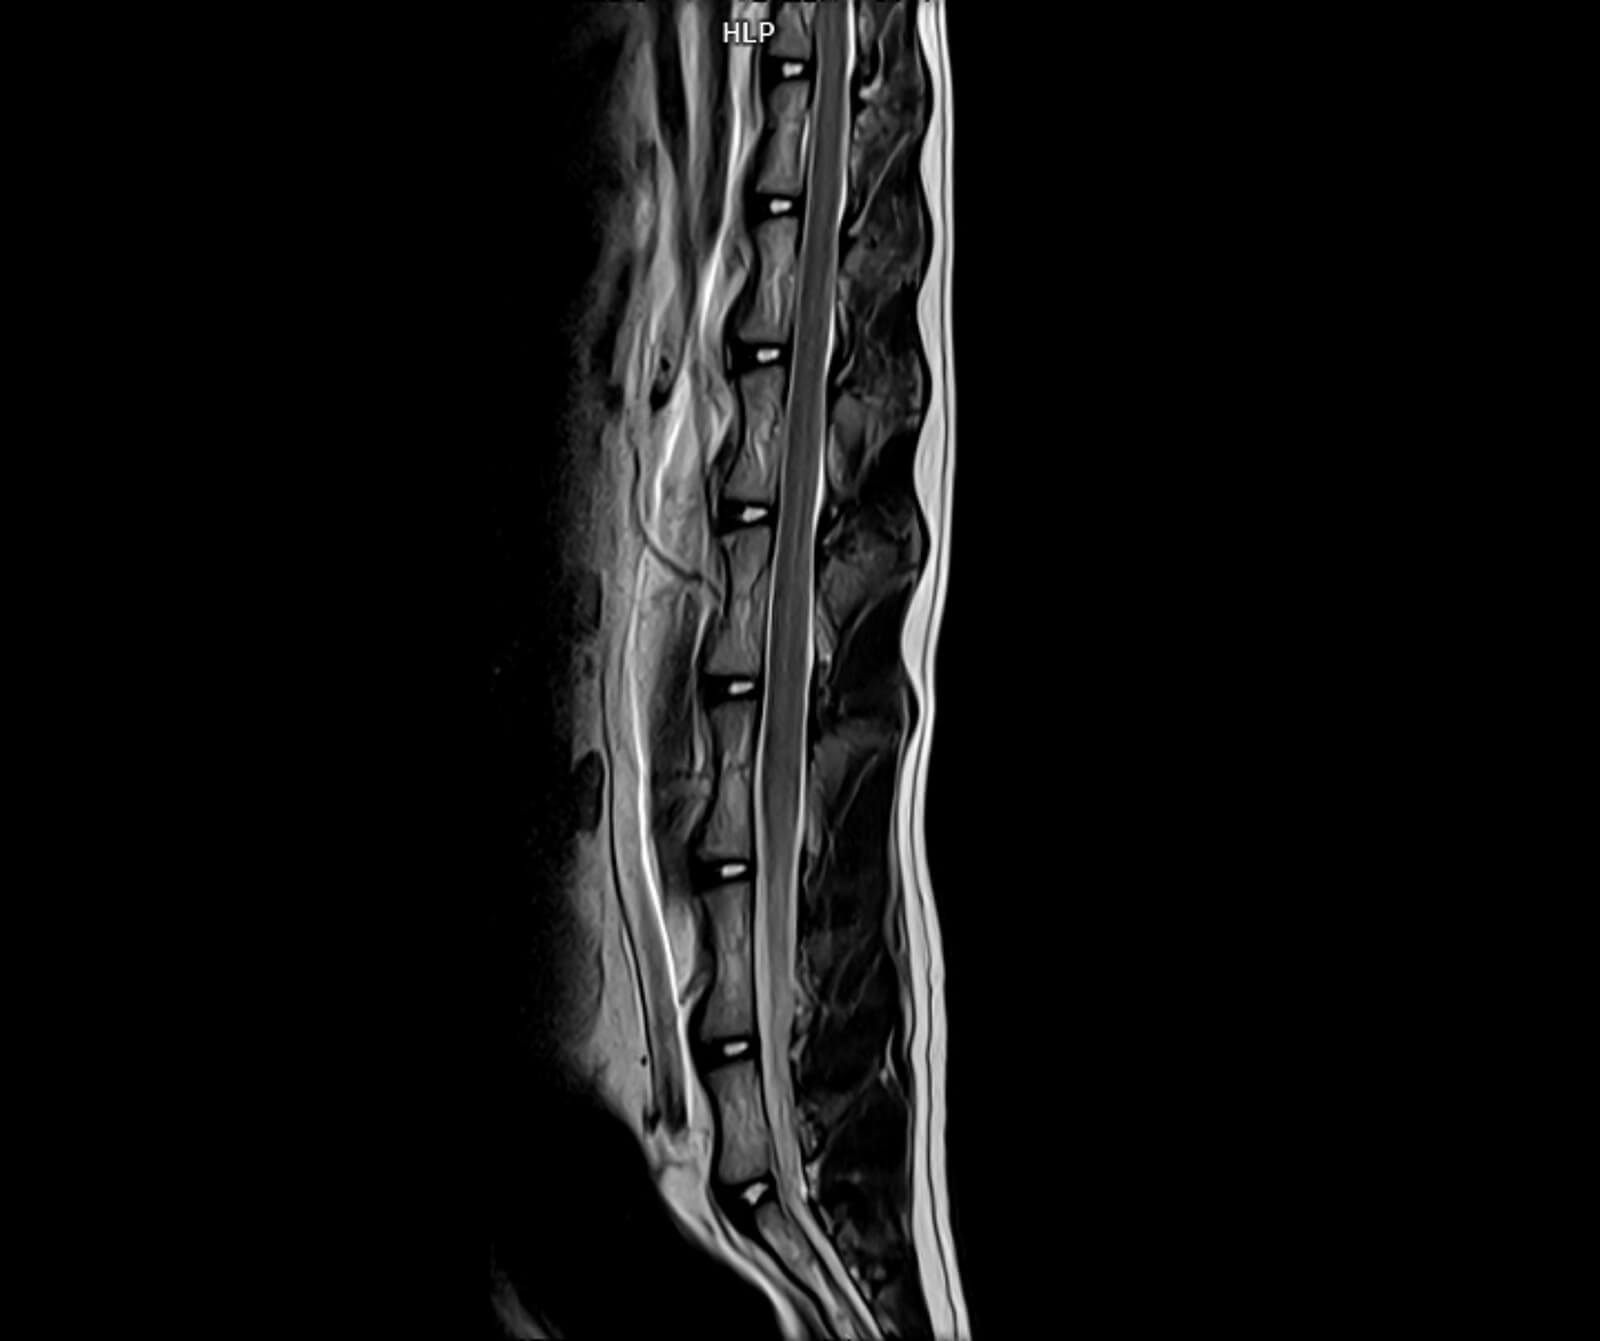

• Spinal kord incelemeleri

• Disk hernisi, omurga tümörleri, enfeksiyonlar ve spinal stenoz

• Omurilikte travmatik ve dejeneratif değişiklikler